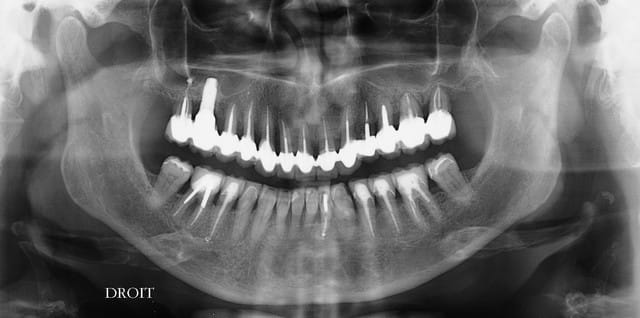

des nouvelles de ce cas, ou l'os devait disparaitre et les céramiques casser....pour le moment c'est intact, et les 3 semaines sont passées...je ne considère pas avoir gagné, mais je n'ai pas perdu non plus :-))

Se sim pano du 19.06 - Eugenol

Se sim 09 02 2016 hnouhj - Eugenol